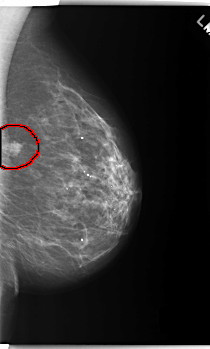

C_0218_1.LEFT_MLO

LEFT_MLO LINES 5928 PIXELS_PER_LINE 3560 BITS_PER_PIXEL 12 RESOLUTION 50 OVERLAY

FILE: C_0218_1.LEFT_CC.OVERLAY

TOTAL_ABNORMALITIES 1

ABNORMALITY 1

LESION_TYPE MASS SHAPE LOBULATED MARGINS ILL_DEFINED

ASSESSMENT 5

SUBTLETY 4

PATHOLOGY MALIGNANT

TOTAL_OUTLINES 1

BOUNDARY